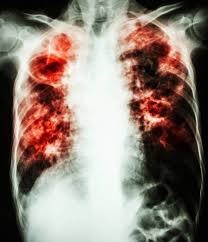

Réduire la morbidité et la mortalité associées aux soins pédiatriques de la tuberculose

L’identification et la prise en charge de la tuberculose chez les enfants

Augmenter l’accès aux nouvelles Formulation à Dose Fixe (FDC) de médicaments anti tuberculeux pédiatriques